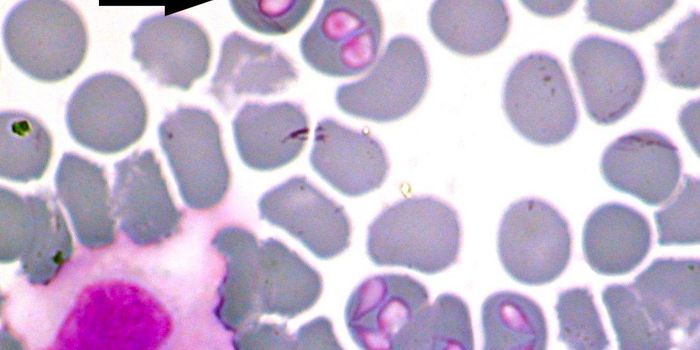

MAR 17, 2017Health & MedicineThe first human case of babesiosis was reported in 1957; until then it was thought of as a disease plaguing domes ...

MAR 24, 2015MicrobiologyThe malaria parasite Plasmodium falciparum produces chemical compounds called terpenes that give off odors that attract ...